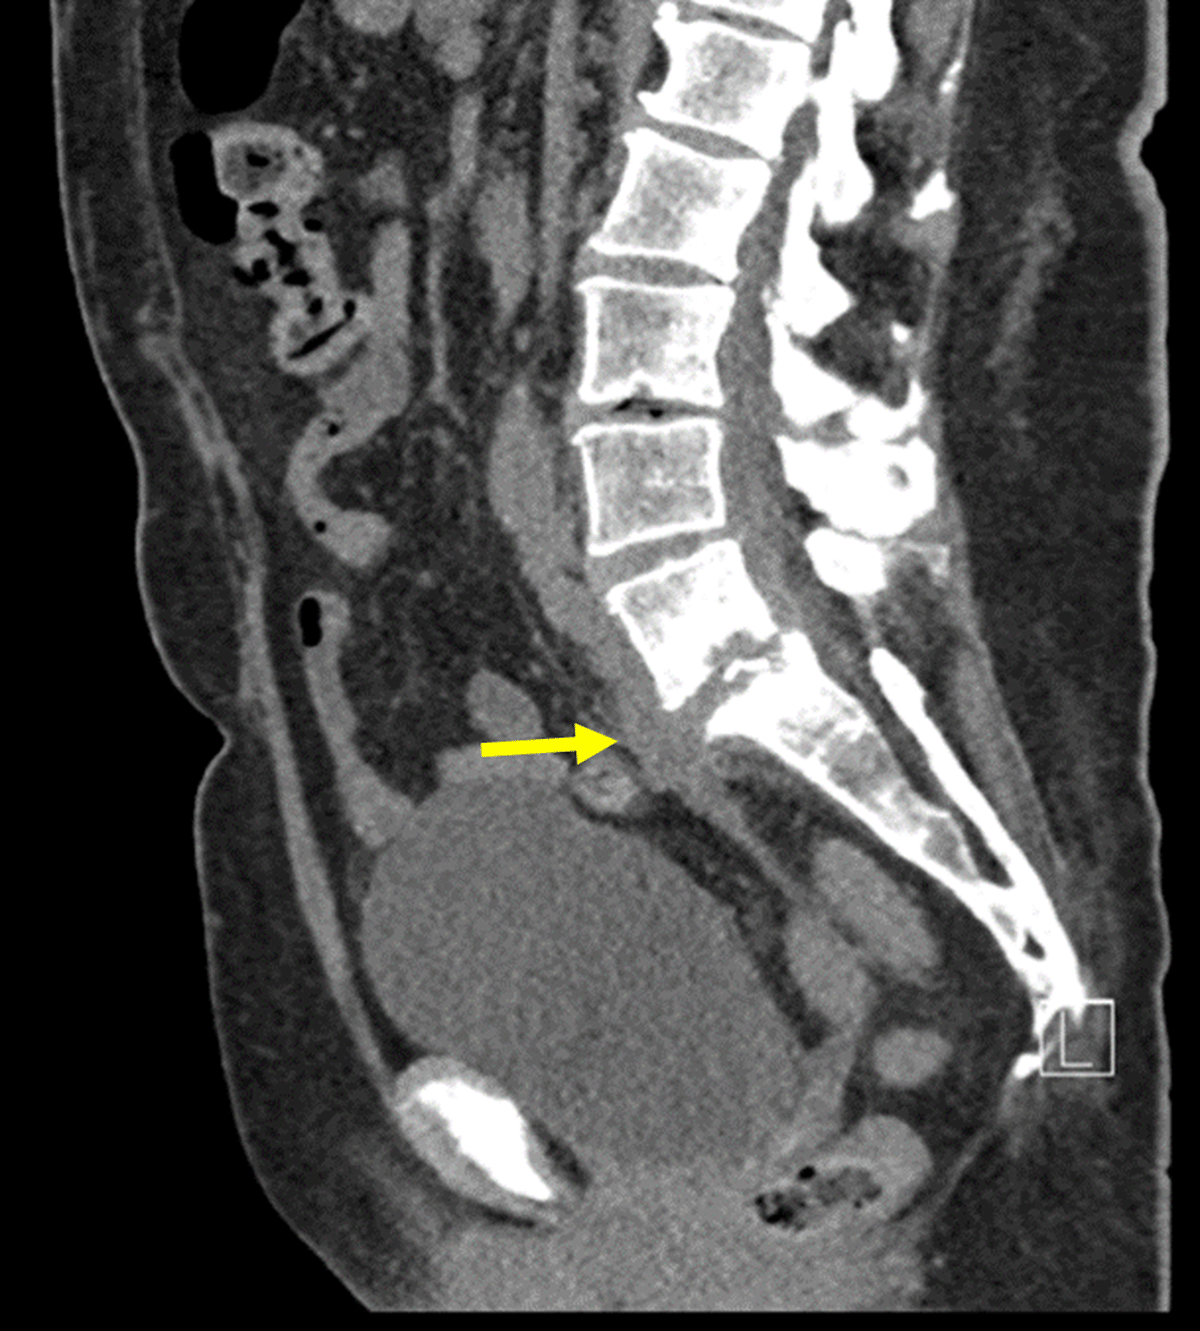

Figure 1

Sagittal non-contrast CT of lumbar spine: Initial CT-scan showing collection from L5-S1 disk with fistulation downwards, an anterolisthesis of L5-S1 with inter-apophysary posterior arthritis and a compression of the right root of S1 by the intervertebral disk.